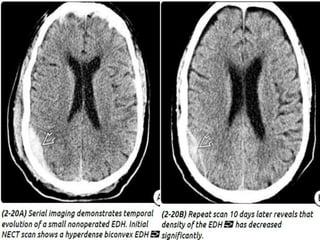

 CT - classic (arterial) EDHs is a hyperdense (60-

90 HU) biconvex extraaxial collection (2-18).

 CT -classic (arterial) EDHs is a hyperdense (60- 90 HU) biconvex extraaxial collection (2-18). Presence of a hypodense component ("swirl" sign) is seen in about one-third of cases and indicates active, rapid bleeding with unretracted clot. “Buckling" the gray-white matter interface inward. Air in an EDH occurs in approximately 20% of cases and is usually associated with a sinus or mastoid fracture.

 Within 24-36 hours following the initial

traumatic event, repeat CT should be obtained

if there is sudden unexplained clinical

deterioration, regardless of initial imaging

findings.